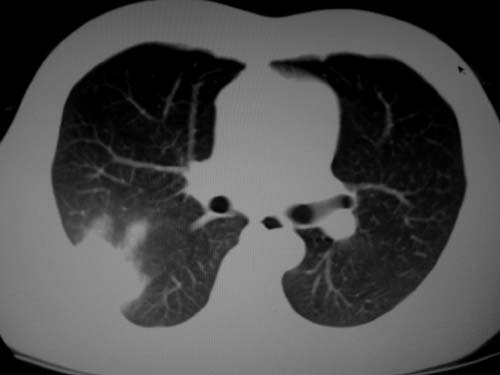

标题: CT19540: 31岁。自述结核性胸水治疗两个月后,在外院拍x线发 [打印本页]

右侧胸壁结节状软组织影伴相应肺叶内受侵,伴右侧胸腔积液。考虑:结核性可能大。

1、炎性包块;2、右侧少量胸膜积液。

支持 右侧胸壁结节状软组织影伴相应肺叶内受侵,伴右侧胸腔积液。考虑:结核性可能大。

1、炎性病变,结核可能;2、右侧少量胸膜积液。

病灶也是发生于结核球好发部位,支持结核

考虑结核性结节

多考虑包裹性胸腔识液。

右侧胸壁结节状软组织影伴相应肺叶内受侵,伴右侧胸腔积液,结合临床,首先考虑结核。

考虑结核性胸膜炎,胸膜肥厚,不除外胸膜间皮瘤可能,建议复查。

支持结核,胸膜间皮瘤不排除.

1)考虑右侧结核性胸膜结节。2)右侧胸膜增厚+包裹性胸腔积液。

结核性脓胸、肺内结核?